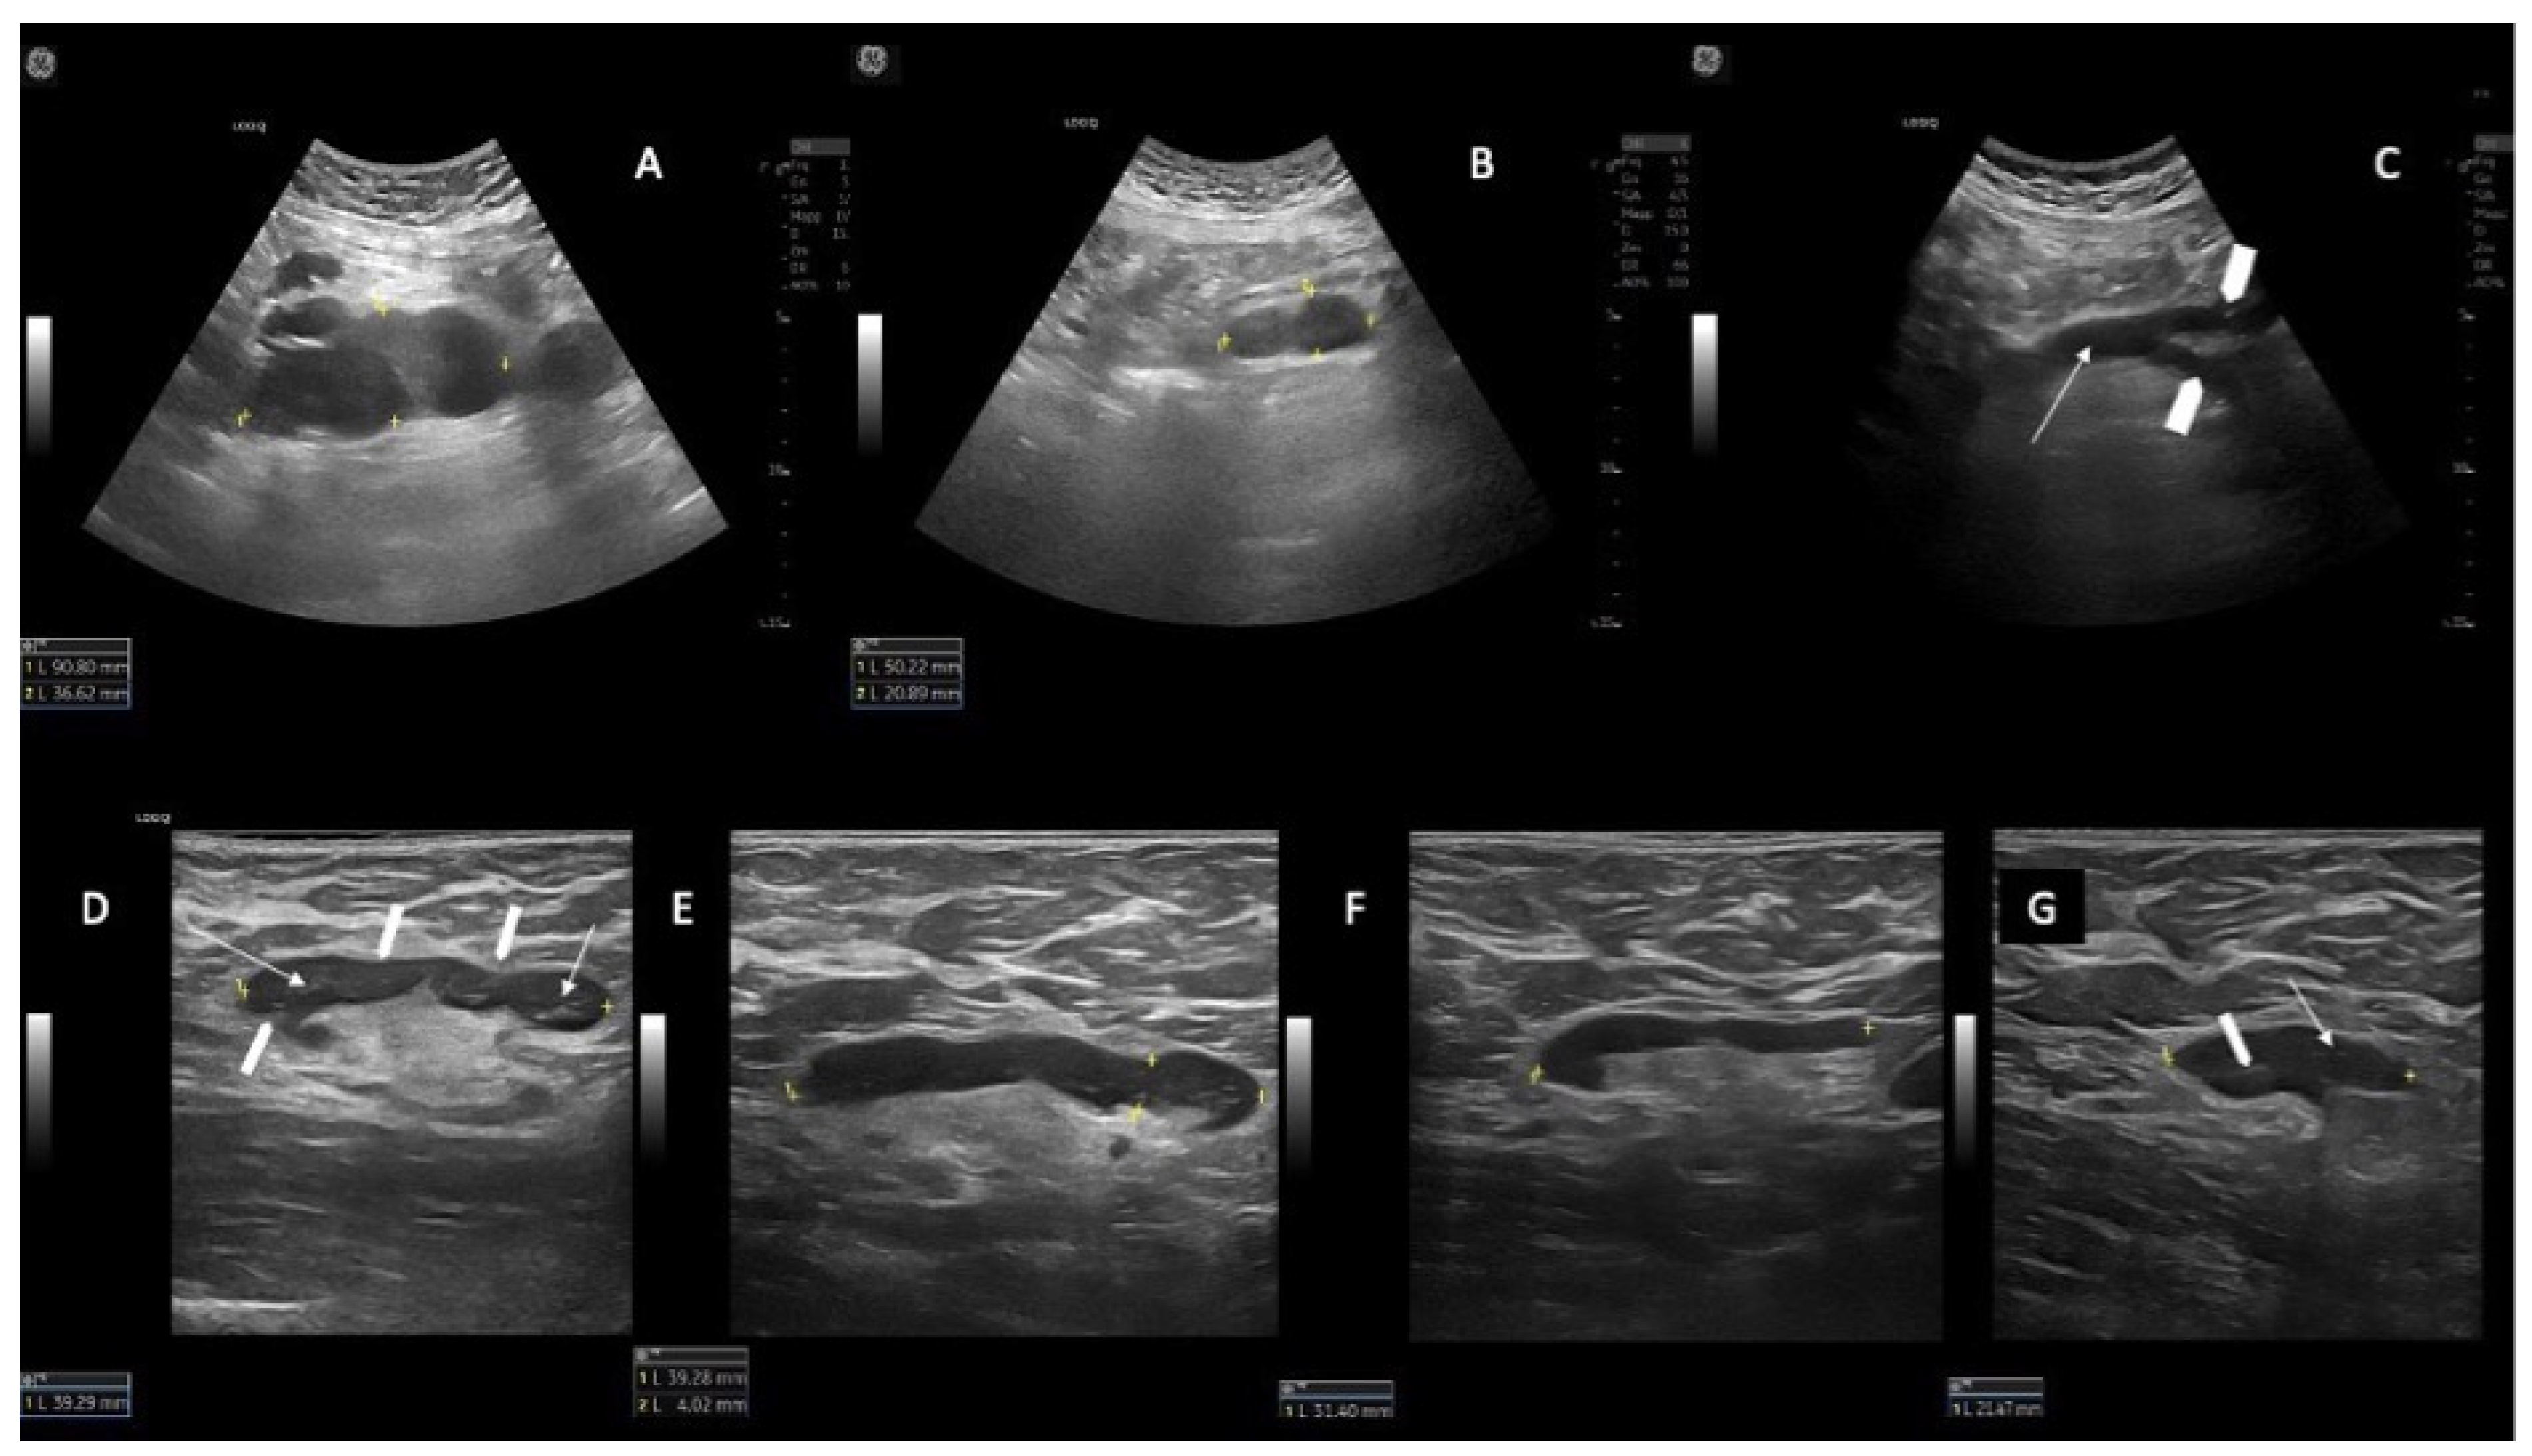

3.5. Lymphnodes Dimensions and Response

3.7. Additional Observations